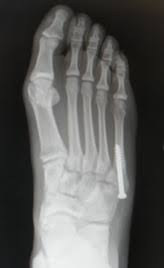

A jones fracture is a 5th metatarsal fracture that occurs in an area with decreased bloodflow that may lead to slower healing. The recovery time was about 4 weeks in a walking. Jones fractures are named after sir robert jonestrusted source , an orthopedic surgeon who in 1902 reported on his own injury and the injuries of several people he. The midfoot gets no respect. Fractured my heel in a fall on sept. About 75% of people in the u.s. Historically, acute 'jones' type fractures as well as the stress fracture were treated in a cast of however, it was noted that healing was particularly poor with both types of fracture. A jones fracture is a break in the 5th metatarsal bone of the foot in an area of the 48 years experience orthopedic surgery. A jones fracture is a break between the base and middle part of the fifth metatarsal of the foot. This is an ap view of a percutaneous jones fracture surgery. These are notorious for very slow healing. Well find out exactly how to get this bone feeling better! Limit unnecessary walking or standing for the first week to control swelling.

Fifth Metatarsal Fracture from geominesbtp.e-monsite.com The midfoot gets no respect. They occur at the intersection between the base and the shaft of the fifth metatarsal. The recovery time was about 4 weeks in a walking. Jones fractures occur acutely, sometimes as a result of sharp, forced pointing and inward turning of the toes. 5th metatarsal fracture recovery time: A jones fracture is a break involving the base of the 5th metatarsal bone. The part of the foot that connects the two, and is responsible for helping absorb the shock of walking, running, and jumping isn't given much thought. This is an ap view of a percutaneous jones fracture surgery.